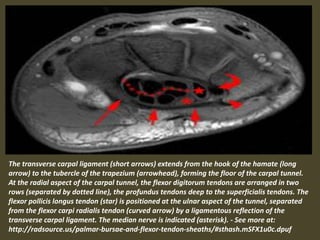

The transverse carpal ligament (short arrows) extends from the hook of the hamate (long

arrow) to the tubercle of the trapezium (arrowhead), forming the floor of the carpal tunnel.

At the radial aspect of the carpal tunnel, the flexor digitorum tendons are arranged in two

rows (separated by dotted line), the profundus tendons deep to the superficialis tendons. The

flexor pollicis longus tendon (star) is positioned at the ulnar aspect of the tunnel, separated

from the flexor carpi radialis tendon (curved arrow) by a ligamentous reflection of the

transverse carpal ligament. The median nerve is indicated (asterisk). - See more at:

http://radsource.us/palmar-bursae-and-flexor-tendon-sheaths/#sthash.mSFX1u0c.dpuf